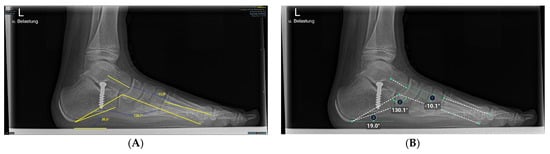

2.5. Anatomic Definitions

The hallux valgus angle is determined by the axis of the first metatarsal bone that of the proximal phalanx [23,32].

Having intersected the axis of the first metatarsal bone with the axis of the second metatarsal bone, the 1st-2nd metatarsal angle was obtained [23,32].

The intersection of the axes of the 1st metatarsal and 5th metatarsal resulted in the third and last angle examined, the 1st-5th metatarsal angle [23].

Figure 3. Illustration of hallux valgus angle, 1st–2nd metatarsal angle, and 1st–5th metatarsal angle measurements on x-ray images in the dorsoplantar plane. (A) Manual measurement exemplary. The same x-ray image was processed by the AI. (B) shows the angles calculated by AI.